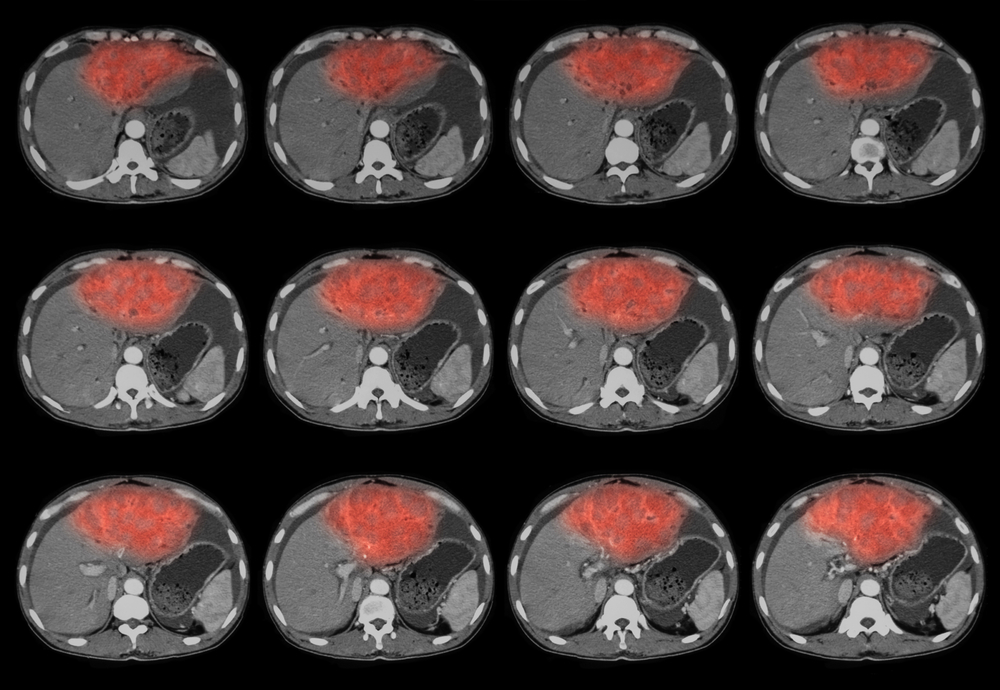

Для уточнения диагноза и определения места локализации и количества абсцессов пациенту назначаются следующие инструментальные диагностические методы:

- рентгенография – выявляются просветления (одно или несколько) с уровнем жидкости, ограничение подвижности диафрагмы и/или признаки излития экссудата в плевральную полость;

- УЗИ гепатобилиарной системы – возможно определение полостей с гнойным содержимым (жидкостью и сгустками) и их размеров;

- МРТ или МСКТ (часто может дополняться контрастированием) – выявляется топография, размеры абсцессов и характер поражения окружающих тканей и органов;

Наиболее информативными методами диагностики абсцесса печени является МРТ (магнитно-резонансная) или МСКТ (мультиспиральная компьютерная) томография печени. При сомнительных данных они могут дополняться радиоизотопным сканированием. В особо сложных клинических случаях пациенту назначается выполнение диагностической лапароскопии. При выявлении в ходе исследования гнойных абсцессов врач одномоментно может принимать решение о проведении операции по их дренированию.